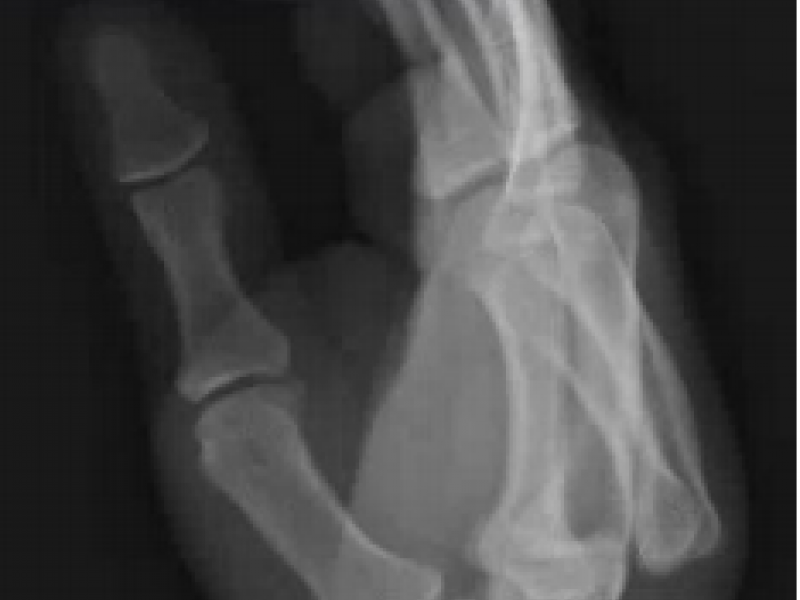

A 35 yo M presents to the ED complaining of R hand pain